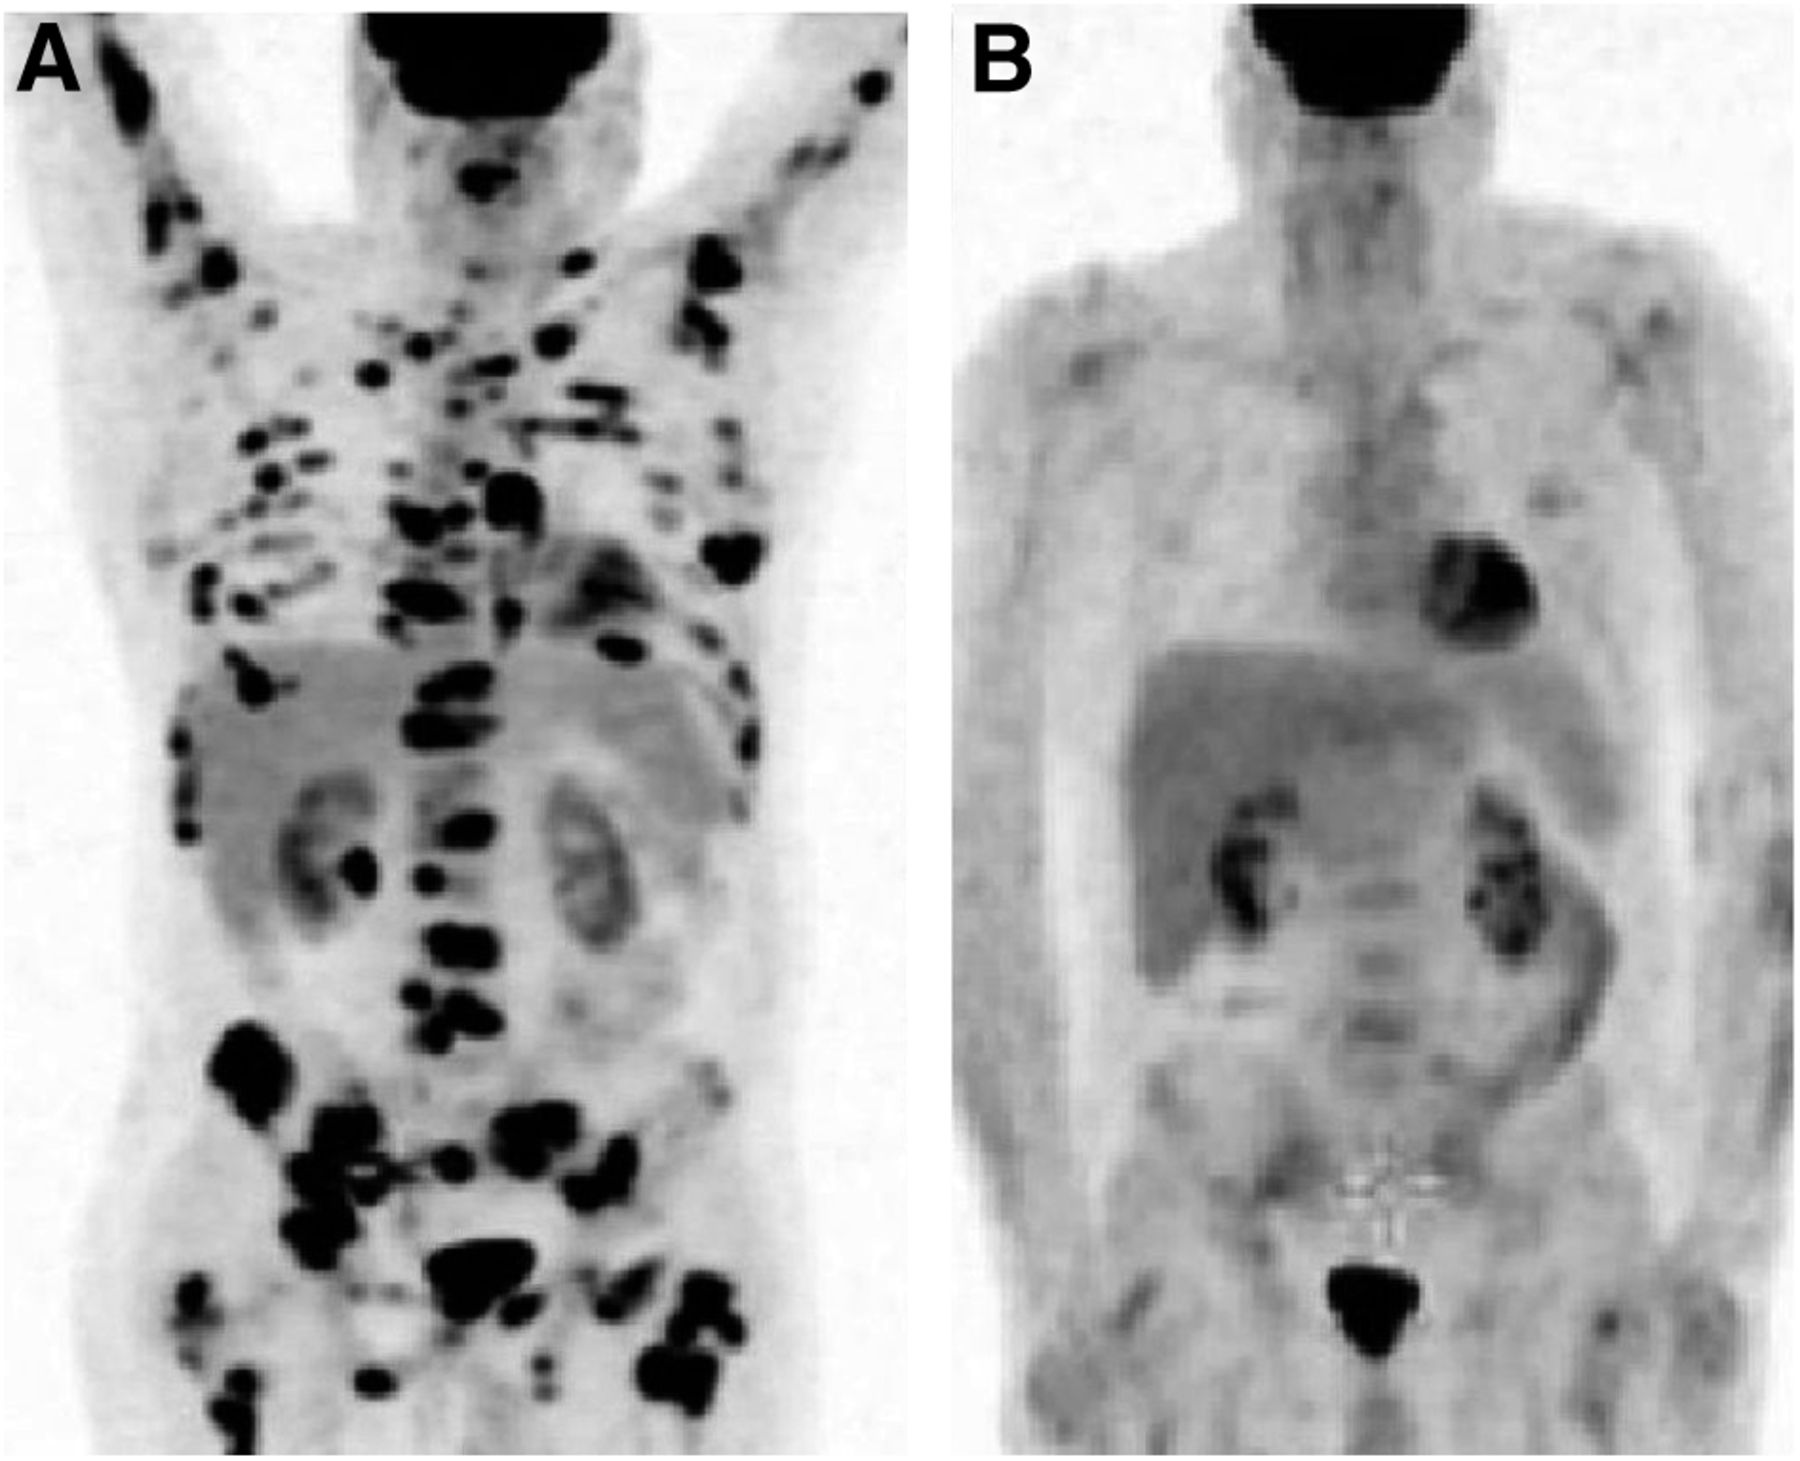

In Newly Diagnosed Diffuse Large B Cell Lymphoma Determination Of Bone

Comparison Of 18F FDG PET And Bone Scintigraphy In Detection Of Bone

Comparison Of 18F FDG PET And Bone Scintigraphy In Detection Of Bone